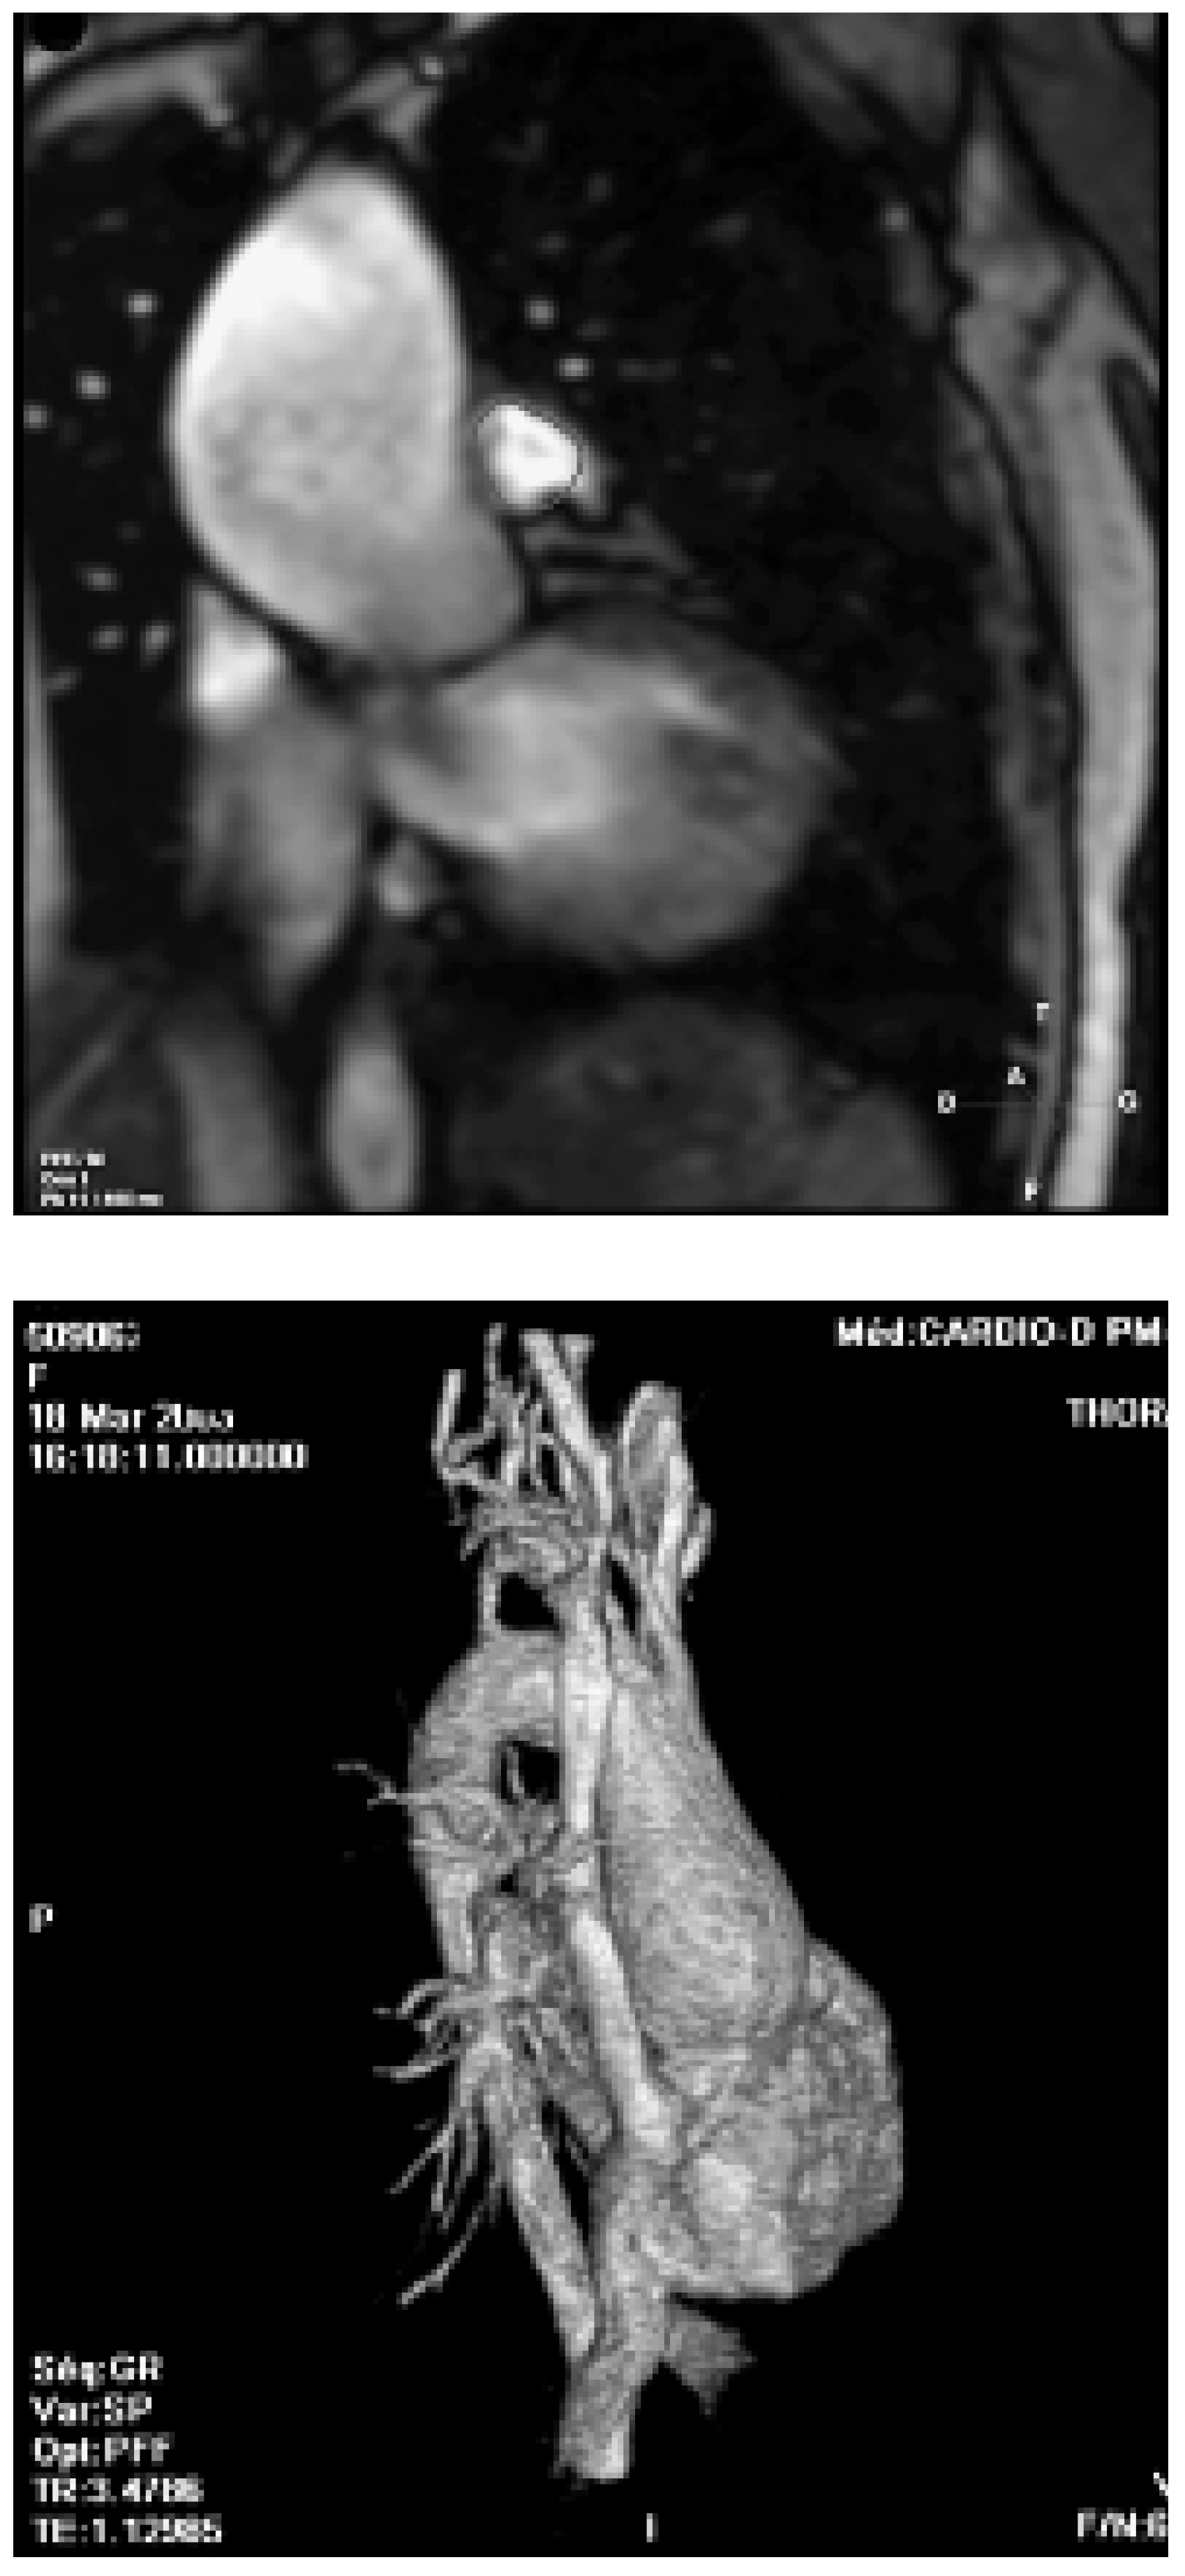

- Vliegen, H.W.; van Straten, A.; de Roos, A.; et al. Magnetic resonance imaging to assess the hemodynamic effects of pulmonary valve replacement in adults late after repair of tetralogy of Fallot. Circulation 2002, 106, 1703–1707. [Google Scholar] [CrossRef]

- Davlouros, P.A.; Kilner, P.J.; Hornung, T.S.; et al. Right ventricular function in adults with repaired tetralogy of Fallot assessed with cardiovascular magnetic resonance imaging: Detrimental role of right ventricular outflow aneurysms or akinesia and adverse right-to-left ventricular interaction. J Am Coll Cardiol. 2002, 40, 2044–2052. [Google Scholar] [CrossRef] [PubMed]

- Niwa, K.; Siu, S.C.; Webb, G.D.; et al. Progressive aortic root dilatation in adults late after repair of of tetralogy of Fallot. Circulation 2002, 106, 1374–1378. [Google Scholar] [CrossRef]

- Oosterhof, T.; Nollen, G.J.; van der Wall, E.E.; et al. Comparison of aortic stiffness in patients with juvenile forms of ascending aorta dilation with-vs-without the Marfan syndrome. Am J Cardiol. 2005, 95, 75–77. [Google Scholar]